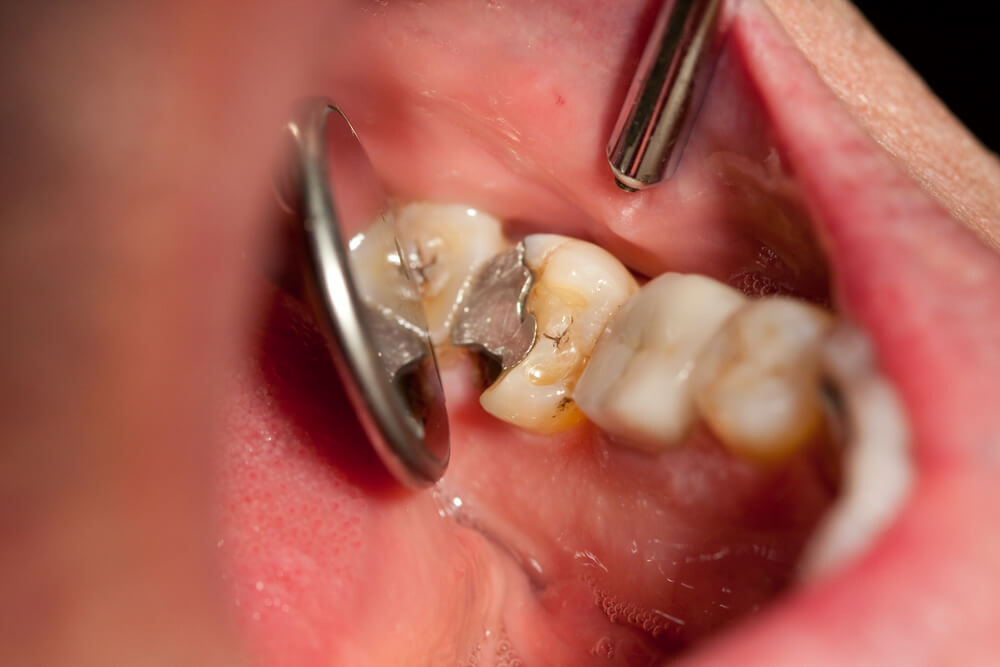

Cavities are pretty common. As the National Institutes of Health points out, the only condition more common than a cavity is the common cold. If you've never experienced tooth decay, you might wonder, "What does a cavity feel like?" The answer depends on the stage of the cavity and what foods you eat. Some foods, such as sweets, might trigger the pain of a cavity more than others.

How Cavities Form

Your mouth is naturally full of germs. Some of those germs are perfectly healthy, but others can be harmful. When you eat something sugary, such as candy or even potato chips, or drink a sugary beverage, the germs feed on the sugars in the substance. This produces acid, which is strong enough to wear away tooth enamel if not cleaned off quickly enough. In the end, a dental cavity begins to form.

Signs of a Cavity

What does a cavity feel like? In the earliest stages, the answer might be nothing. There are no nerves in your tooth enamel, so when the decay is in that layer, you likely won't feel a thing. Once the decay has progressed enough to reach the softer tissues inside the tooth, where the dentin and nerves are, you might notice signs of a cavity. Your teeth might feel sensitive and you could feel some pain, especially after eating sweets, hot foods or cold foods. The pain can be fairly mild or sharp and intense. Some people with cavities also feel pain when biting down.

Depending on the size of the cavity, you may be able to see evidence of it in your mouth. Cavities sometimes create visible holes in the teeth. They can also create stains that are black, brown or white on the surface of the tooth.

Cavities and Sweets

Why are you more likely to feel pain from a cavity when you eat sweets? Some foods, including sweets, are more likely to cause pain when there is enamel erosion. Sweet foods tend to be sticky, so they often cling to your teeth. The germs that feed on them can then produce more acid, which can make its way into the cavity, irritating the nerves. Even if you don't have a cavity, sugary foods will cause more sensation in sensitive teeth.

Seeing Your Dentist

What should you do if you think you have a cavity? The first step is to see your dentist. Although cavities can be reversed in the early stages, by the time you are feeling discomfort or pain, only a dentist can treat them. An x-ray will be taken to determine how the cavity has progressed into the tooth. Depending on how severe the cavity is, you might need a filling to fix it. If the decay is very severe, the dentist might replace the tooth with a crown or perform a root canal.

Even if you're not sure if you have a cavity, regular professional cleaning and dental visits are important. A dental hygienist can apply a fluoride treatment to help strengthen the teeth and reverse the very early stages of decay. He or she can also give you tips on the best ways to brush your teeth and advise you about what foods to avoid or consume less frequently to reduce your risk for cavities. As with many conditions, when it comes to cavities, taking preventative steps is a lot easier than treating the problem down the road.